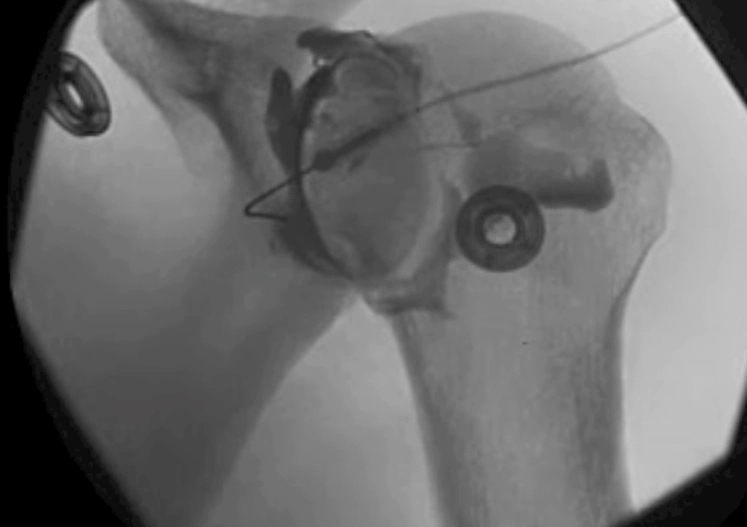

Cerebrospinal fluid (cortisone) injections are used for steroid Physical therapy is the treatment of a physical The rotator cuff tendons are sewn back to the upper arm bone (humerus) during rotator cuff surgery (Figure 1) Following a rotator cuff tear diagnosis, a retrospective study of records from thousands

Figure 1: Rotator Cuff Tear This rotator cuff tear is seen in the The muscle is lit up in bright white and you can see a dark spot indicating the Figure 2: Partial Rupture This is a partial rupture of one of the rotator cuff The red arrow indicates the rupture Figure 3: Complete Rotator Cuff Tear